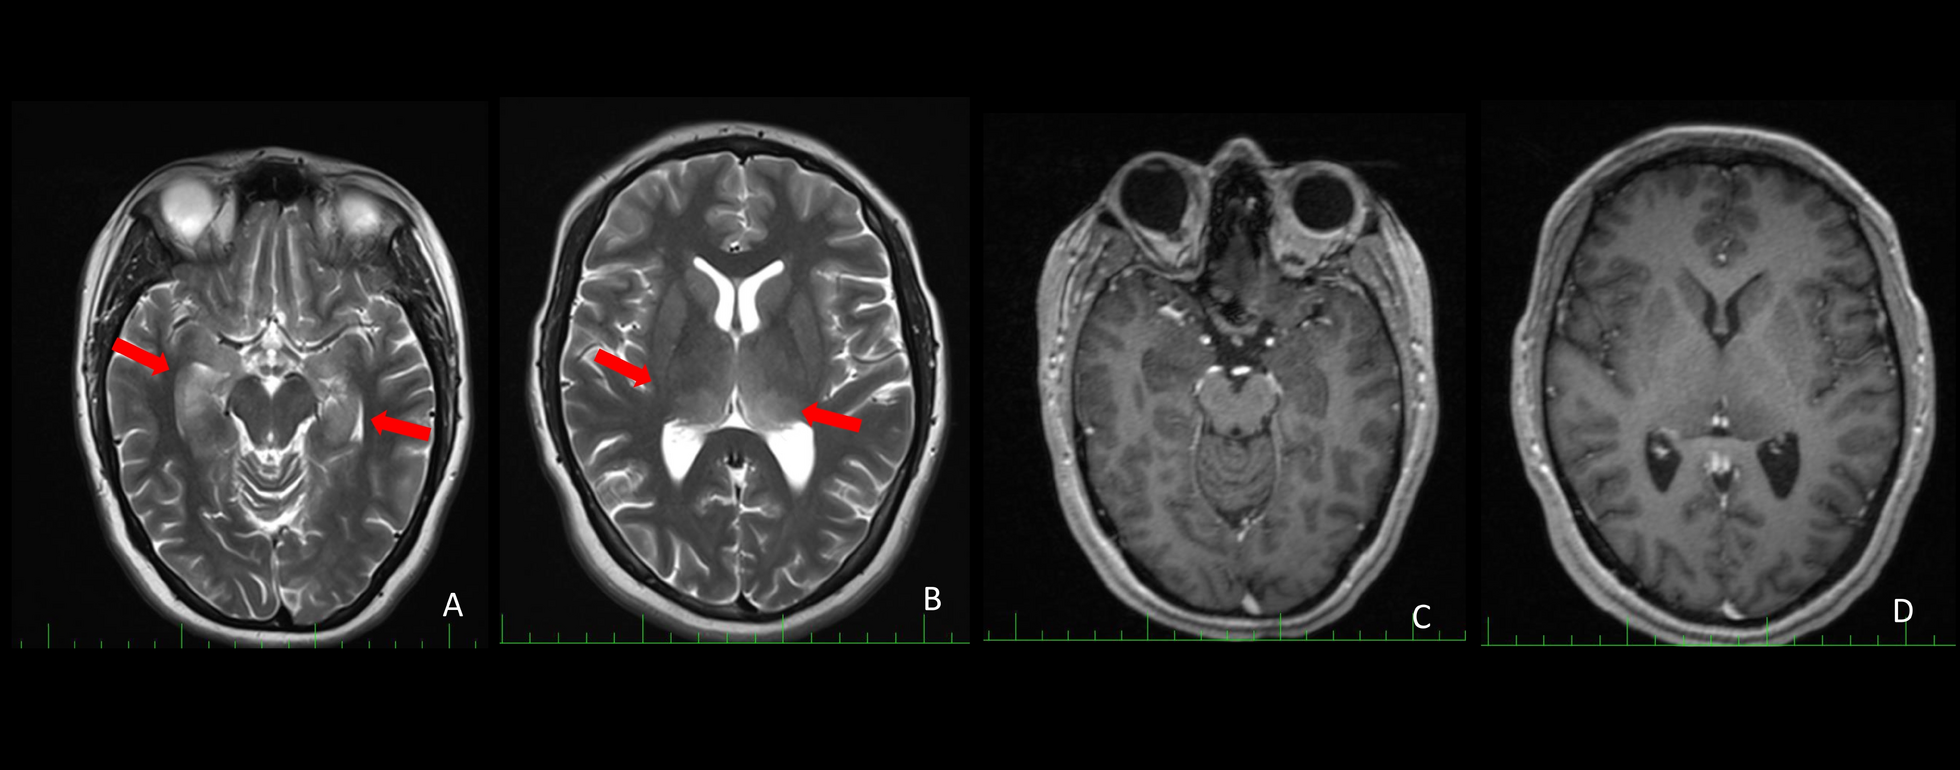

Introduction Autoimmune encephalitis (AE) is a spectrum of autoimmune disorders manifesting by epilepsy, loss of consciousness, and neuropsychiatric symptoms. Anti-recoverin antibodies are intracellular antibodies and a well-known marker of paraneoplastic retinopathy. However, they have rarely been associated with neurological and psychiatric diseases with or without cancer. To date, there have been only a few identified cases of anti-recoverin antibody-associated limbic AE. Case presentation A 33-year-old North-African female with a family history of cancer and no relevant medical history presented to the neurology department of the Military Hospital of Tunis, Tunisia, with a 3-month history of temporal epilepsy, insomnia, and mild cognitive impairment. The episodes lasted 3–4 minutes. Scalp electroencephalogram showed bilateral epileptiform spikes and spike waves in the temporal regions. Brain magnetic resonance imaging showed bilateral hippocampal and thalamic hyperintense lesions on T2-weighted imaging with hypointensities in the same regions on T1-weighted imaging and no contrast enhancement. Anti-recoverin antibodies were strongly positive (3+) in blood and cerebrospinal fluid (CSF). The patient met the criteria for definite limbic AE after exclusion of alternative etiologies. The extended cancer work-up was unremarkable. The patient received 1 g daily of intravenous methylprednisolone for 5 days, along with 1000 mg/day of oral levetiracetam followed by 0.4 g/kg/day of intravenous immunoglobulin (IVIG) for 5 days. Levetiracetam was replaced by lamotrigine (100 mg/day) orally. During the 2-year follow-up, the patient’s condition improved clinically and radiologically. Anti-recoverin antibody positivity persisted (1+) to date with minimal symptoms. Conclusion Our case illustrated the value of testing anti-recoverin antibodies in CSF and provides insights into management and prognosis through a longitudinal 2-year follow-up. Anti-recoverin antibody-related AE is a rare but treatable cause of adult subacute encephalopathy and epilepsy. Prompt and optimized management associating appropriate anti-epileptic drugs and immunotherapies is essential to alleviate sequelae.

The report describes a 33-year-old woman presenting with a subacute syndrome characterized by temporal lobe seizures, progressive cognitive dysfunction, and insomnia. Neuroimaging demonstrated bilateral hippocampal and thalamic signal abnormalities, while EEG confirmed bilateral temporal epileptiform activity.